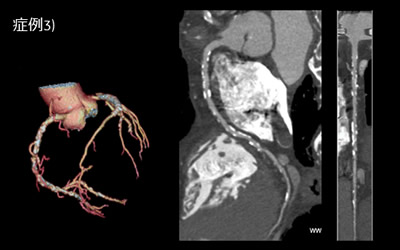

症例3) 70歳台 男性

大動脈弁狭窄症 及び 狭心症

術前の検査でTAVIやPCIの検討のためCTを施行した。

従来冠動脈の石灰化が著しい例では冠動脈CTの意義は低いとされていたが、石灰化が強い例でも明瞭な冠動脈の描出がなされれば、意義のある検査となることが視覚的にもわかりやすい例である。